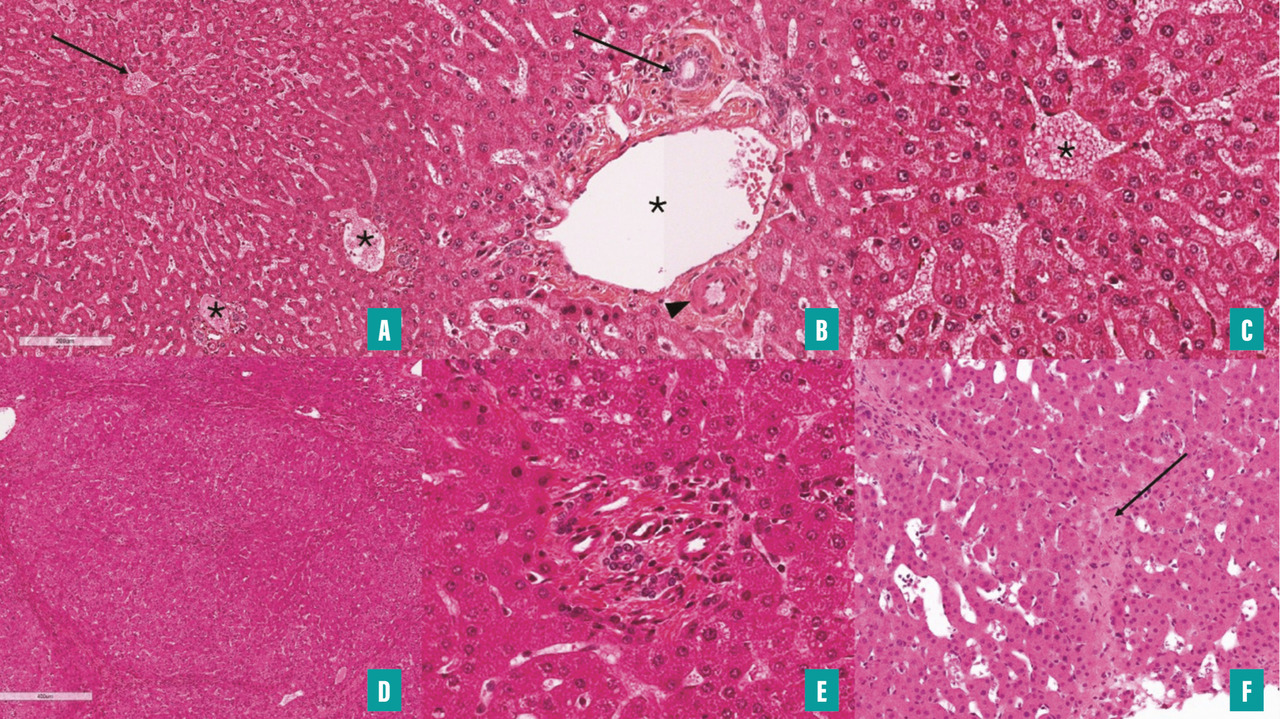

Dans ce contexte, le pathologiste a une place prépondérante pour le diagnostic de la maladie vasculaire. Il doit analyser pas à pas la biopsie en portant une attention toute particulière aux vaisseaux. Tout d’abord, une biopsie de suffisamment bonne qualité est nécessaire pour établir le diagnostic de maladie vasculaire. Cette biopsie doit mesurer au moins 15 mm et, en dehors de la cirrhose, au moins dix espaces porte complets sont nécessaires pour considérer le prélèvement comme de qualité suffisante.10 Outre l’identification des caractéristiques morphologiques élémentaires suggérant des anomalies vasculaires, l’analyse de la biopsie hépatique permet d’estimer l’étendue de ces anomalies et leur chronicité grâce à l’évaluation de la fibrose et des distorsions architecturales.11

L’évaluation histologique de la biopsie hépatique repose sur l’analyse de coupes sériées. La coloration standard à l’hématoxyline-éosine (HE) ou à l’hématoxyline-éosine-safran (HES) permet d’étudier la plupart des caractéristiques histologiques  ; une coloration du tissu conjonctif (coloration de Picro-Sirius ou trichrome de Masson) est également réalisée. La coloration de la réticuline fournit une évaluation plus précise de l’architecture hépatique que l’HE/HES, ce qui est particulièrement utile pour mettre en évidence les processus de régénération dans un contexte de maladie vasculaire.

L’interprétation de la biopsie hépatique repose, comme pour les autres maladies du foie, sur une analyse systématique des différentes structures morphologiques du foie, avec une attention spécifique pour les espaces portes et en particulier les veines portes, les veines centrolobulaires et les sinusoïdes (voir critères analysés dans la figure 4).10 En particulier, une atteinte des veines portes et des sinusoïdes fait discuter une maladie vasculaire porto-sinusoïdale tandis qu’une atteinte des veines centrales et des sinusoïdes fait évoquer les diagnostics de syndrome de Budd-Chiari ou encore de syndrome d’obstruction sinusoïdale (fig. 5).